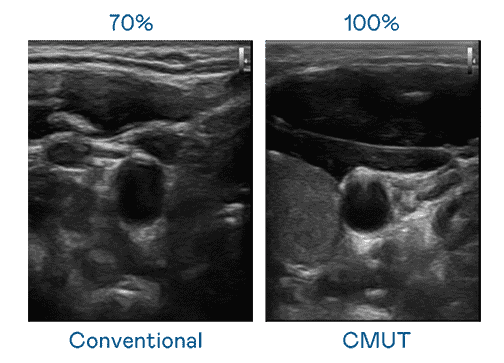

CMUT 技术是一种用电容式微机电元件来产生超音波讯号的技术。。。与传统 PZT 压电式技术相比,,CMUT 频宽增加 30%,,,,更宽频的超音波讯号让影像解析度大幅提升,,,是实现高影像品质医疗超音波扫描、、、、促进精准医疗发展的关键技术。。。。

超音波影像的解析度高低,,,,首先取决于探头能发出的讯号频宽。。918.COM CMUT 可提供高清晰的超音波讯号,,,提供高频宽、、高灵敏度、、、影像纹理细节更高的超音波影像,,,,协助医护人员缩短影像判读时间及利用精准的医疗影像进行诊断。。